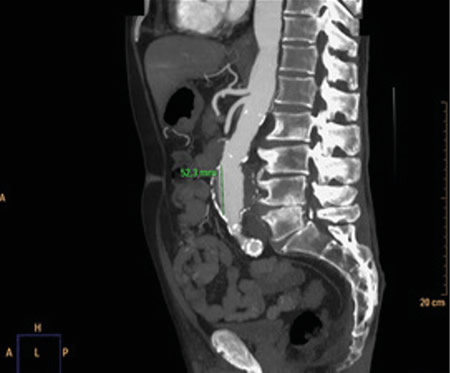

Figura 2